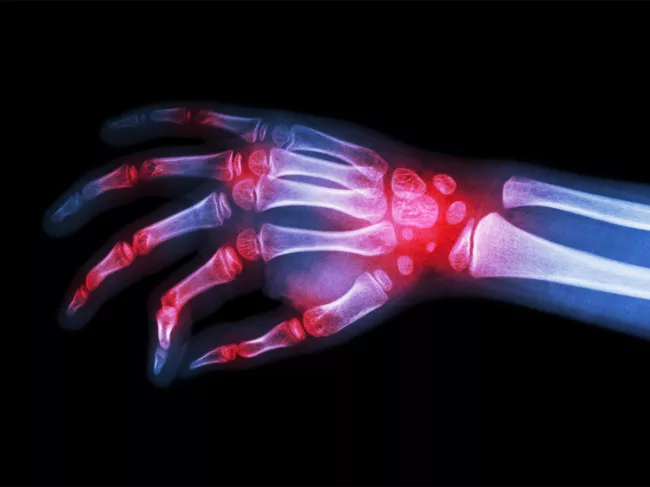

X-ray image of hand and wrist

T cells store lipids and die in rheumatoid arthritis joints

In the inflamed joints of rheumatoid arthritis, CD4+ T lymphocytes accumulate lipid droplets that make them vulnerable and promote their death, thereby amplifying joint inflammation. A study led by scientists at Mayo Clinic and Stanford University suggests that blocking the formation of these lipid droplets or their contents could offer a therapeutic strategy for this condition. Read More